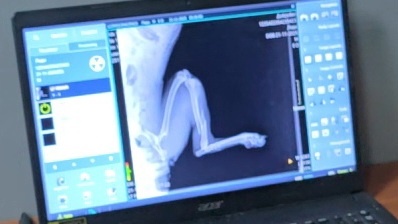

Леди... Назвали её так неслучайно. Даже в такой ситуации она ведёт себя как истинная леди - терпеливо, без упрёков, без злобы на мир, который так жестоко с ней обошёлся. Машина не просто сбила её - она раздробила лапку так, что ветеринар покачал головой, глядя на рентгеновский снимок.

рентген показывает серьёзный перелом лапы собаки

Этот снимок... Когда я увидела эти белые осколки на тёмном фоне, в горле встал комок. "Сложно будет", - тихо сказал врач. И знаете что? В такие моменты я ненавижу эту фразу больше всего на свете. Мучить? А кто её мучил до этого, оставив бродить по дорогам? Кто мучил, когда не подумал о стерилизации? Кто создал ситуацию, где собаки вынуждены искать еду возле трассы?